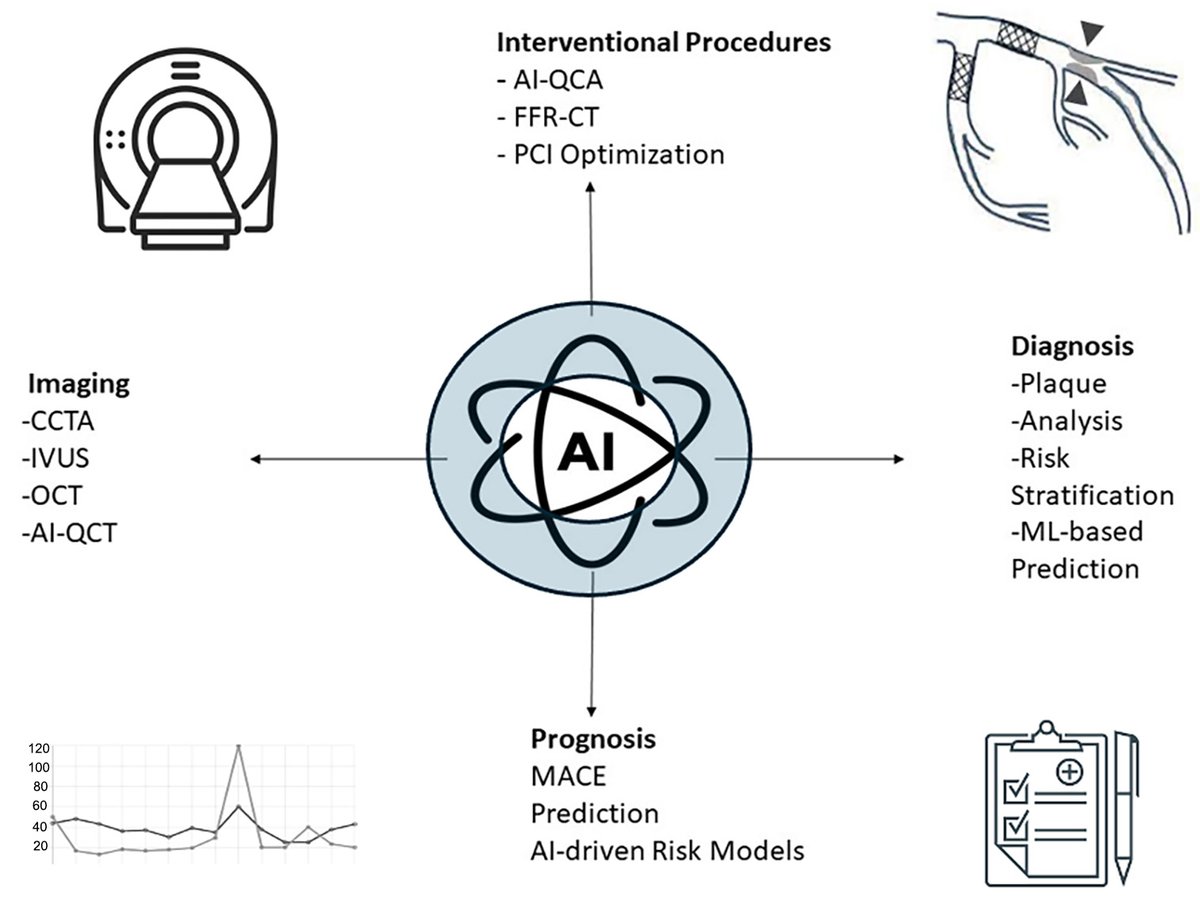

AI boosts precision in interventional cardiology but requires real-world validation. #ImagingAI #ClinicalAI #CardioInnovation @adrianocaixeta @drandrewsharp @rickytiago @DrSheilaSahni @TheNarulaSeries @MichaelMegalyMD @Pushpendraamu @JeremyKingPCI @alma_palau @kevinjamescroce

✨ AI in Interventional Cardiology 🤖 Improves imaging & plaque detection ⚙️ Aids planning, risk stratification 🌐 Needs validation & ethics #InterventionalCardiology #AI #PlaqueImaging 🔗 oaepublish.com/articles/2574-…